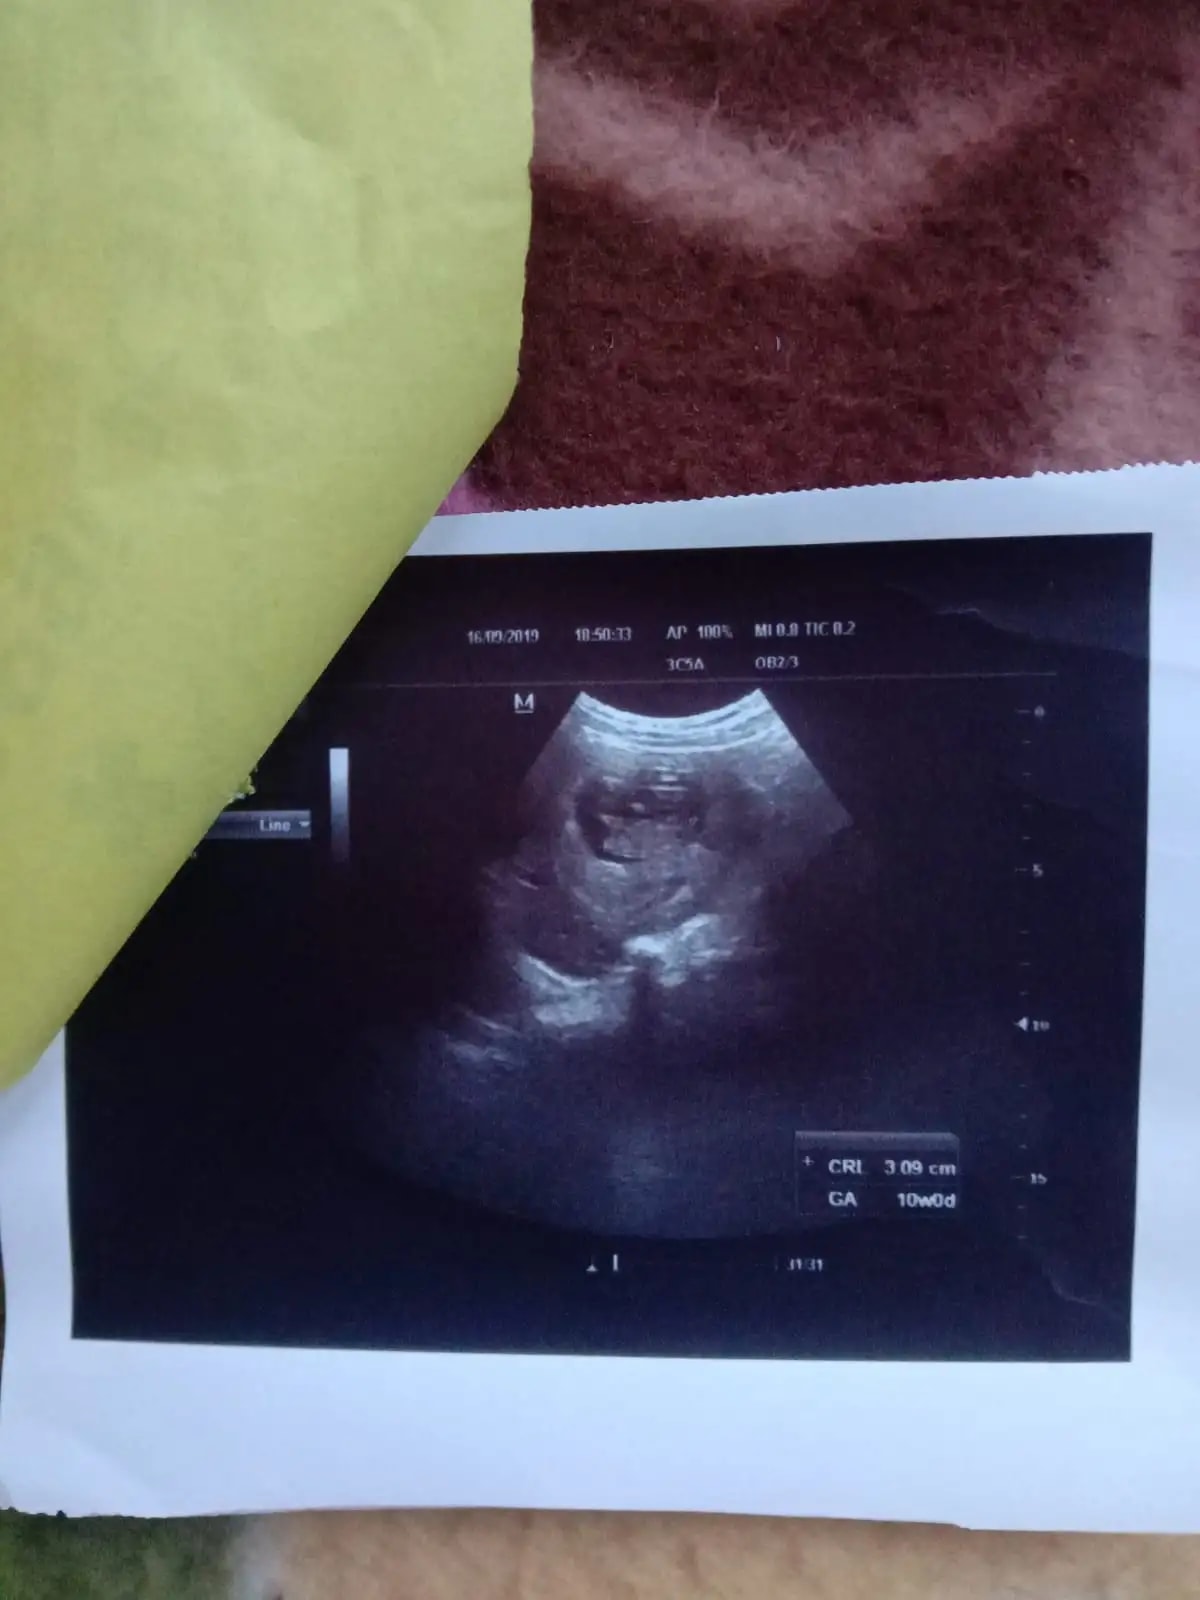

Q: Ye kesi h

A: kon c report h y... See more

A: Report mtlb jo likha hua ho vo send kro dear ... See more

• Hello sisters please meri ultrasound report dekhkar bataiye ki sab Kuch hai .... our meri pregnancy ko kitne din ho gay me bahut confused Hu ....mere hisaab se 7th month abhi start hua hai doctor ne Bola hai ki 7 month complete hone wala hai ..... please help me